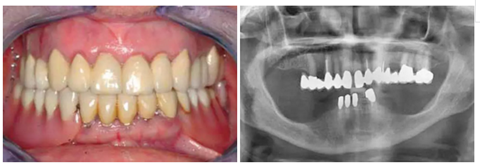

總的來說,72%的拔牙窩集中在上頜骨,而其中的63%是在前牙區(qū)(14-24)。(圖1a & b)

圖1a&b:SP或RP治療的拔牙窩的牙位分布。

有一位病人因為口腔鱗狀細(xì)胞癌而進(jìn)行了部分舌和口底的切除術(shù),并進(jìn)行了輔助放療。盡管由于組織的纖維化,外科準(zhǔn)備及創(chuàng)口縫合時變的非常困難,但患者的種植手術(shù)最終仍然成功了?;颊吲宕髁肆甑牧x齒,并且一直沒有出現(xiàn)問題。這部分的臨床過程及義齒情況詳見于圖8-18.

圖8:一位70歲患者在13計劃行SP 圖9:影像學(xué)顯示13無保留意義。